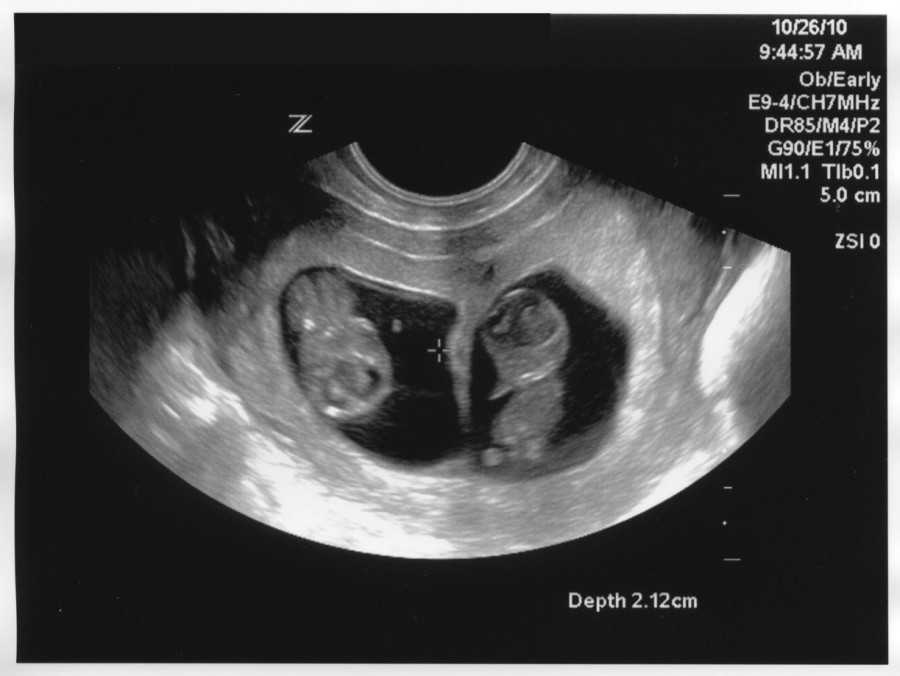

Также показано ультразвуковое исследование плода. Процедура УЗИ позволяет определить срок беременности, толщину плаценты, а также общее состояние яичников и пуповины.

На УЗИ плода на 9 неделе определяется толщина плаценты и общее состояние пуповины. При помощи допплера, будущая мама может отметить частоту сердечных сокращений малыша. Хотя многие внутренние органы уже достаточно развиты, это не всегда можно увидеть на УЗИ на 9 неделе.

Внутренние органы крохи еще могут выступать в виде пупочной грыжи, но нет повода для беспокойства, ведь это совершенно нормальное явление.

На УЗИ на данном сроке обязательным является общая оценка состояния яичников.

УЗИ на сроке 9 недель